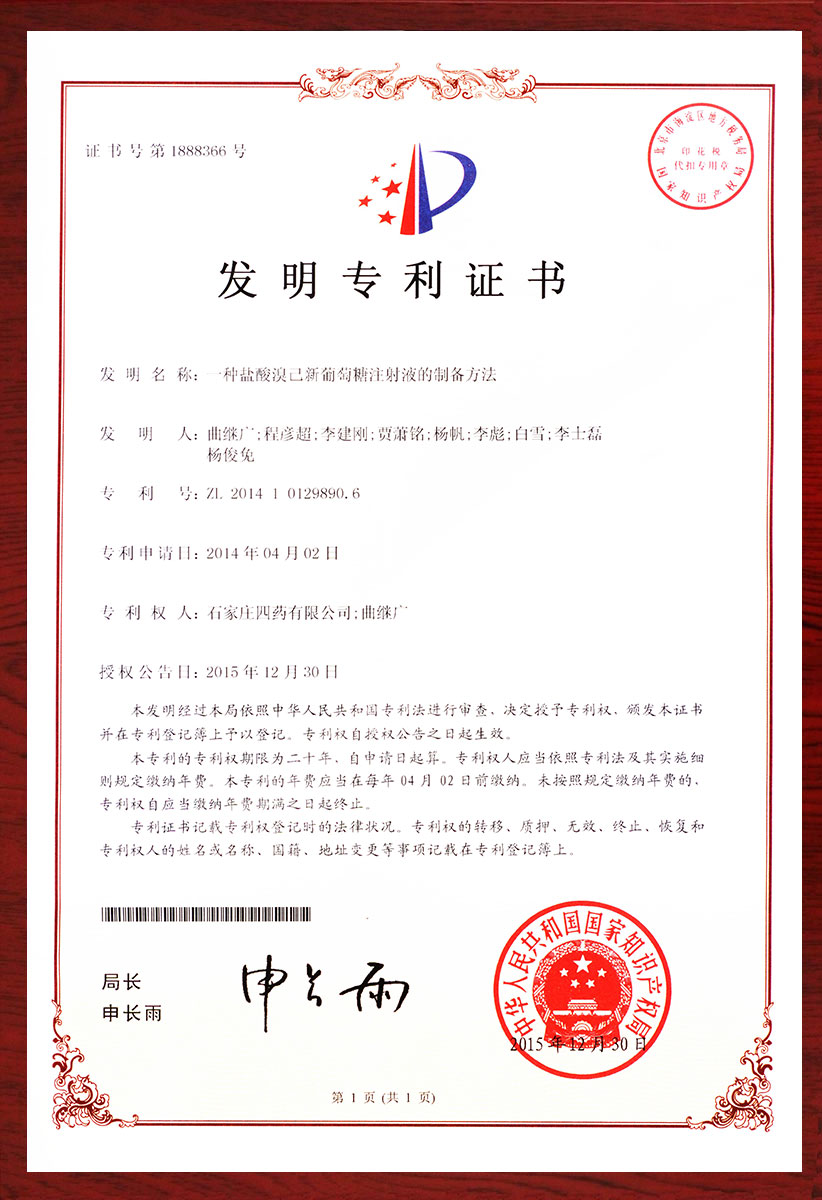

专利证书